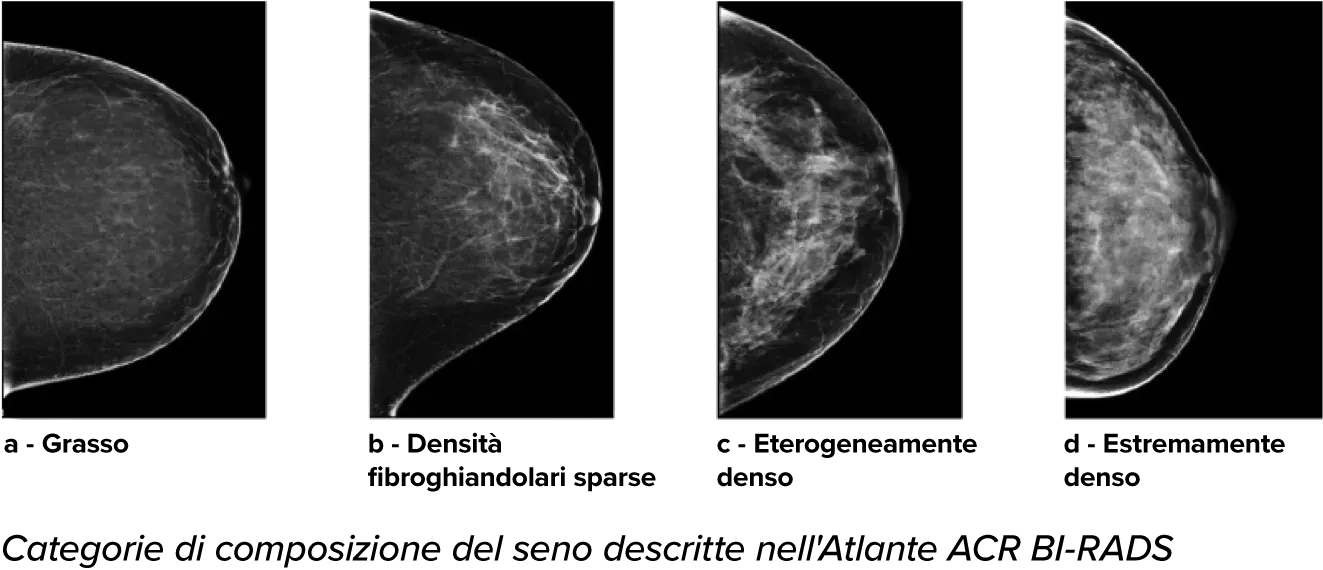

È noto che una maggiore densità del tessuto aumenta il rischio di tumore della mammella.1 È pertanto essenziale effettuare un'analisi accurata e obiettiva. Grazie alle funzionalità di machine learning, il software della tecnologia Quantra analizza le immagini 2D™ e di tomosintesi per evidenziare la distribuzione e l'aspetto del tessuto parenchimale. Classifica le mammelle in quattro categorie in base alla composizione, in linea con le indicazioni del BI-RADS Atlas dell'American College of Radiology (ACR), 5a edizione.2

*I punteggi si basano sulle categorie ACR BI-RADS, in conformità con le linee guida riviste del BI-RADS Atlas dell'American College of Radiation (ACR), 5a edizione. Per determinare la densità si tiene conto della struttura e dell'aspetto del tessuto rispetto al volume.

8. Categorie di densità del tessuto mammario descritte in ACR BI-RADS Atlas.